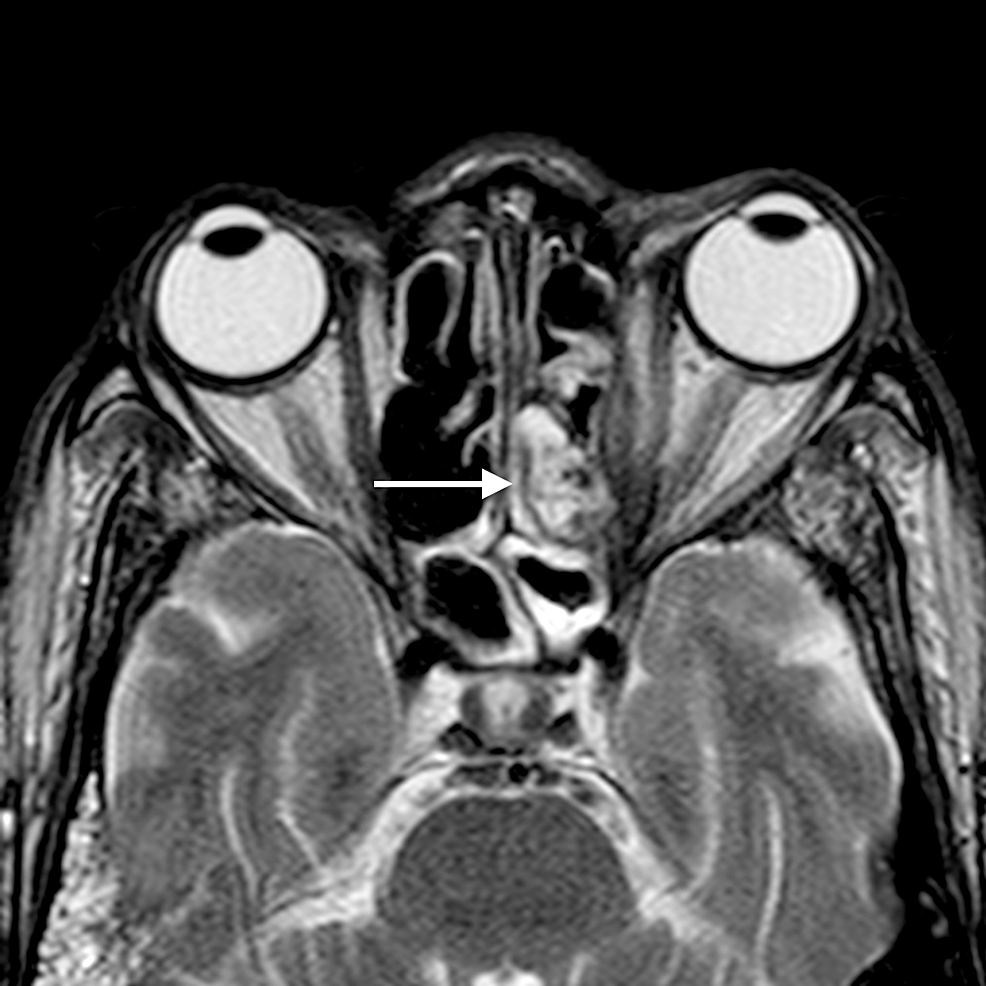

The main complications of orbital cellulitis (Figures 2-4) encountered in our study were:

1. An orbital abscess (Figures 5-6);

2. Preseptal cellulitis and abscess (Figures 7-8);

3. Periorbital cellulitis (Figures 9-10);

4. Dacryoadenitis (Figures 11-12);

5. Optic neuritis/perineuritis (Figure 13);

6. Cavernous sinus thrombophlebitis and thrombosis (Figure 14).

The most common complication of orbital cellulitis was orbital/periorbital abscess formation (eight cases, 53.3%), followed by optic neuritis (four cases, 26.67%), intracranial involvement (four cases, 26.67%), dacryoadenitis (three cases, 20%) and cavernous sinus thrombophlebitis (three cases, 20%).